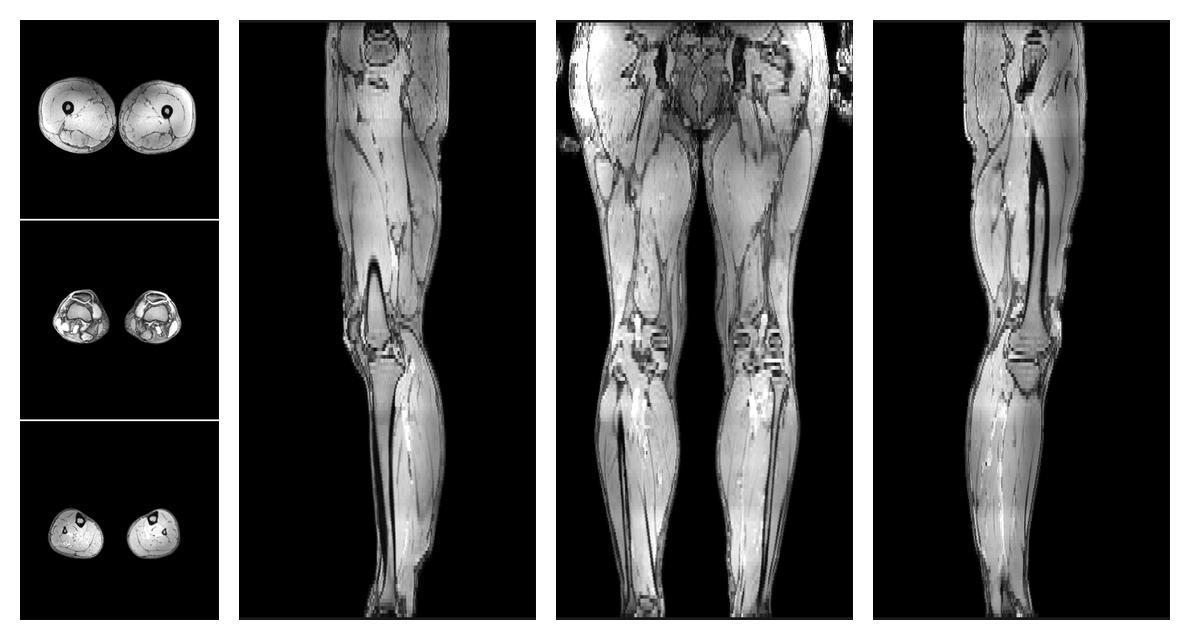

• Water only T2 relaxation time

The water only T2 relaxation time of the lower extremity obtained from multi echo spin echo t2 mapping with EPG based reconstruction.